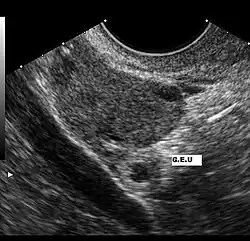

Diagnóstico por la imagen

El ultrasonido es probablemente la herramienta más importante en el diagnóstico de un embarazo extrauterino, especialmente si se combina con otros métodos. Con mayor frecuencia, se utiliza para confirmar un embarazo intrauterino.[15] La visualización de un saco intrauterino, con o sin actividad cardíaca fetal, a menudo es suficiente para excluir un embarazo ectópico.[14] La excepción es en el caso de un embarazo heterotópico, la combinación de embarazos intra y extrauterino que, aunque es una situación excepcional, se ven cada vez más frecuentes, entre 1 de 4000 a 1 de cada 30 000 embarazos espontáneos. El estudio de los anexos uterinos por un ultrasonido es obligatorio en pacientes sometidas a estimulación ovárica y la reproducción asistida a pesar de la visualización de un embarazo intrauterino, porque son pacientes que tienen 10 veces mayor riesgo de embarazo heterotópico.

El ultrasonido transvaginal tiene mayor resolución que el abdominal y puede ser usado para visualizar un embarazo intrauterino 24 días después de la ovulación o 38 días después del último período menstrual, que suele ser alrededor de 1 semana antes de los que es posible visualizar un ultrasonido transabdominal. El saco gestacional —un término ecográfico y no anatómico— es la primera estructura que se reconoce en un ultrasonido transvaginal.[14] Se ve en el ultrasonido como una zona ecogénica gruesa en torno a un centro hipogénico correspondiente a la reacción decidual trofoblástica que rodea el saco coriónico. Las estructuras que representan a un embrión en desarrollo aún no se pueden reconocer sino hasta una mayor edad gestacional.[16]